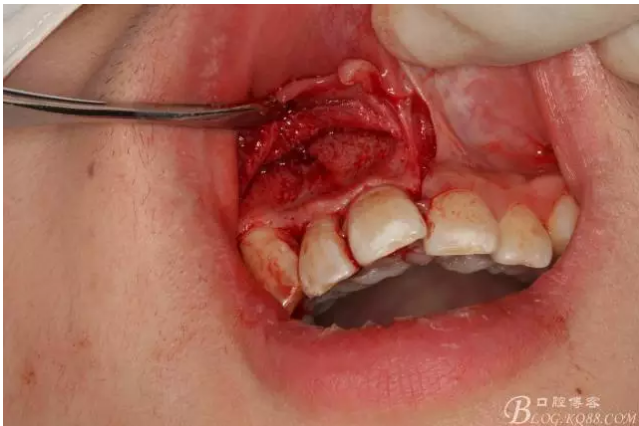

圖2.根管治療術(shù)后直接局部 麻醉下切開(kāi)、翻瓣,發(fā)現(xiàn)12唇側(cè)骨壁有綠豆大小骨缺損

圖3.依缺損部位為中心,逐漸去骨,完整暴露出囊壁。